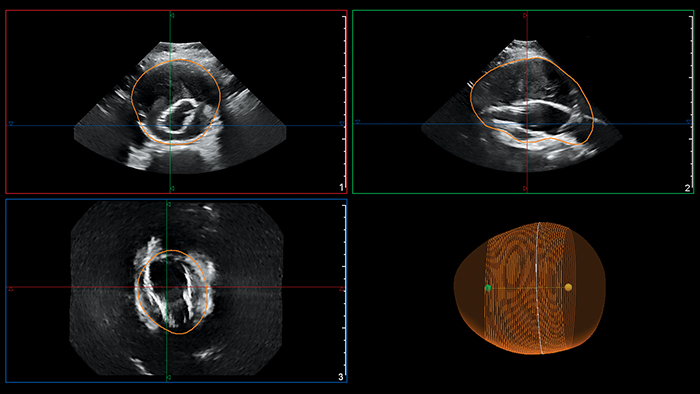

フィリップスの腹部大動脈瘤(AAA)モデルは、3D 超音波データをセグメント化、定量化し、本来の AAA および EVAR 処置後の AAA のサーベイランスに使用できます。

フィリップスの腹部大動脈瘤(AAA)モデルは、動脈瘤の中心線を示し、最大前後(AP)径や部分容積などの主要測定値を提供します。

AAA の最大径は中心線に垂直に測定するのが理想とされていますが、これまでそれが可能なのは 3D CT および磁気共鳴血管造影法(MRA)のみでした⁵。フィリップスの AAA モデルは、ボリュームデータ全体を通して AAA の中心線を示すことにより、この方法を 3D 超音波検査でも可能にしました。